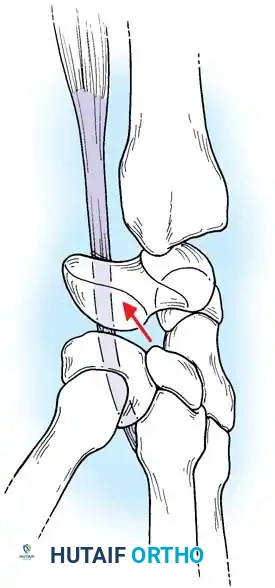

Fig. 66-76 Radioscaphoid ligament (RSL) and surrounding capsular anatomy.

Pathoanatomy and Clinical Presentation

Without the tethering effect of the lunate, the proximal pole of the scaphoid rotates dorsally, assuming a more vertical orientation. Eventually, the scaphoid separates entirely from the lunate.